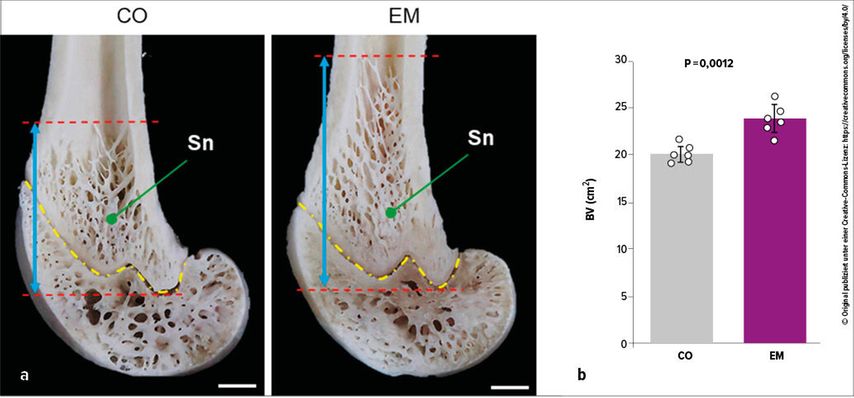

Im Tiermodell steigert die Supplementierung von Eierschalenmembran das Knochenvolumen (Abb. 2) und die Osteoblastenzahl signifikant (p<0,01).10 Zudem wurde auch die Knochenmarksverfettung reduziert.

Abb. 2: (a) Makroskopische Ansicht der distalen Femurmetaphyse. (b) Knochenvolumen (BV) berechnet mittels μCT-Analyse (n=6). Sn: Spongiosa. Blaue Pfeile: longitudinale Breite der Spongiosa. Gelbe Linie: Wachstumsfuge. Rote Linien: oberes und unteres Ende der Spongiosa. Maßstab = 1mm. CO: Kontrolle; EM: Eierschalenmembran (modifiziert nach Yashima N et al.)10